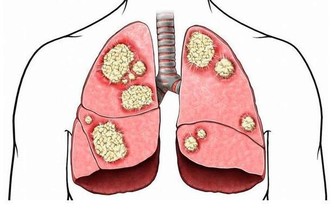

3、肺氣充足

通常說,底氣足的人聲音洪亮,底氣從何而來?從肺氣而來,如果一個人連說話都沒有力氣,就更別提身體健康了。